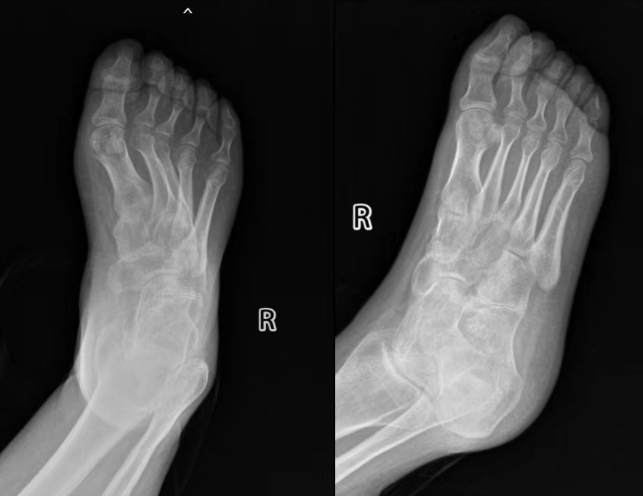

术前X线片